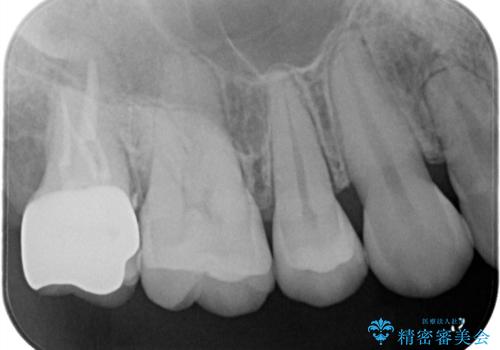

治療前は遠心のポケットが7mmほどありましたが、治療後には3mmに改善しています。